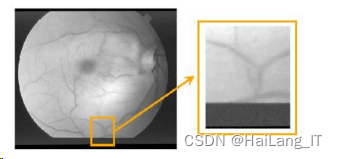

所使用的眼底视网膜血管图像是通过彩色眼底摄影法获得,原图为 RGB 三通 道彩色图像。RGB 三通道图像信息量巨大,理论上相对于单通道灰度图像在计算量上增加了 2 倍,大大降低了神经网络的运行速度。文预处理的第一步是图像灰度转换,将彩色图 像转换为灰度图像,处理效果如图 所示:

如图所示,医学影像边界相对比较模糊,梯度比较复杂,较多的浅层高分辨率 信息有利于目标的精准分割。同时由于人体内部构造相对固定,所需要分割的目标在医 学影像中的分布有一定规律性,对于这些语义信息比较简单的部分可以利用深层低分辨 率信息对其进行目标的识别。

视网膜血管医学影像分割: